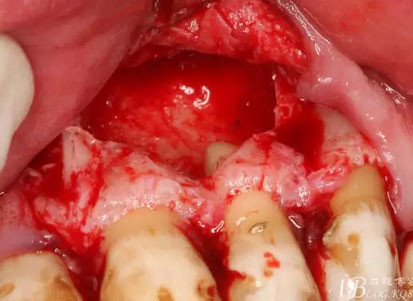

圖14.呼之欲出的囊腫

圖15.摘除的囊壁